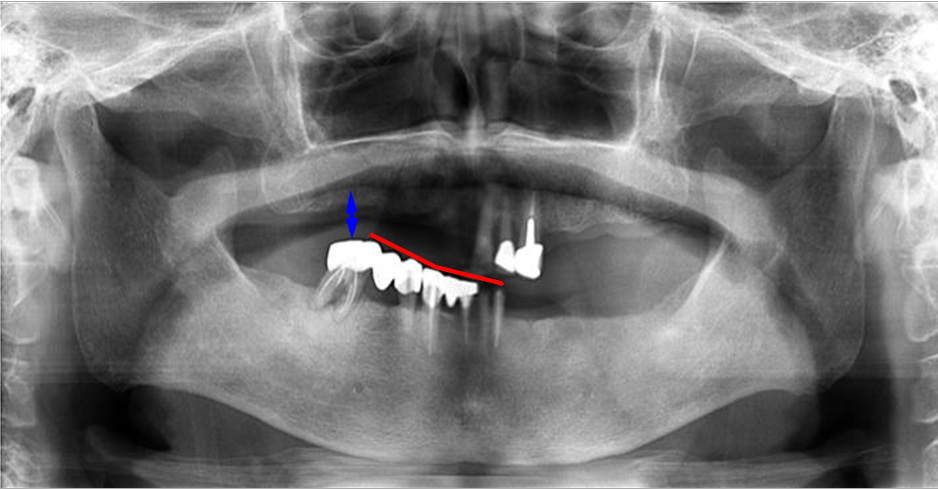

上の2枚のレントゲンは上下奥歯の咬合関係が無く左右前後の咬合崩壊が起きています。

義歯が使えないとの主訴で来院されました。左右、前後、歯の高さは完全に崩壊。

この噛み合わせで義歯を作ったところで、噛み合わせはズレ、義歯を入れるスペースも不足(↕)しています。

義歯を新製はしたが「噛み辛い」「ガタつく」「痛い」は、咬合関係の崩壊を修正せず、基準を無視し新製してしまった症状と大いに考えられます。